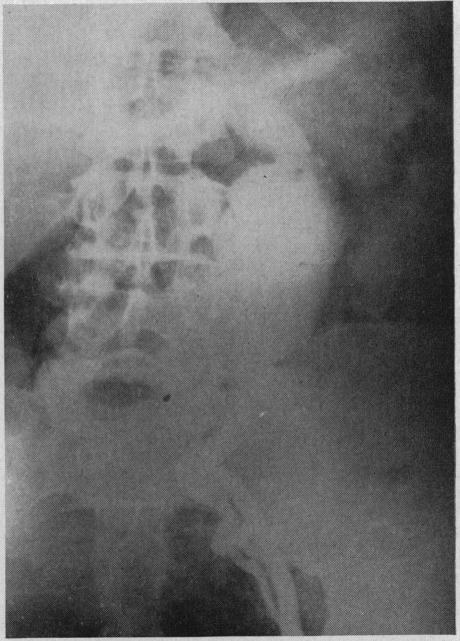

With the use of anticoagulants to prevent recurrence of thrombosis it is now possible to open a major artery which has been occluded by a thrombus, remove the thickened lining with the clot and restore the continuity of the vessel. Free vein grafts have been used successfully to replace arterial segments in the extremities. Vein inlay grafts are preferred in dealing with aneurysms of the abdominal aorta. The aneurysmal wall can be used to support the venous segments. It has been possible to by-pass aneurysms of the abdominal aorta by anastomosing the splenic artery to the left iliac artery. The use of the left superficial femoral artery as a by-pass to supply blood to the right leg is described.

使用抗凝剂预防血栓形成复发后,现在有可能开通一条被血栓阻塞的主要动脉,清除带有血栓的增厚内膜并恢复血管的连续性。游离静脉移植物已成功用于替代四肢的动脉段。在处理腹主动脉瘤时,静脉镶嵌移植物更受青睐。动脉瘤壁可用于支撑静脉段。通过将脾动脉与左髂动脉吻合,有可能绕过腹主动脉瘤。文中描述了使用左股浅动脉作为旁路为右腿供血的情况。